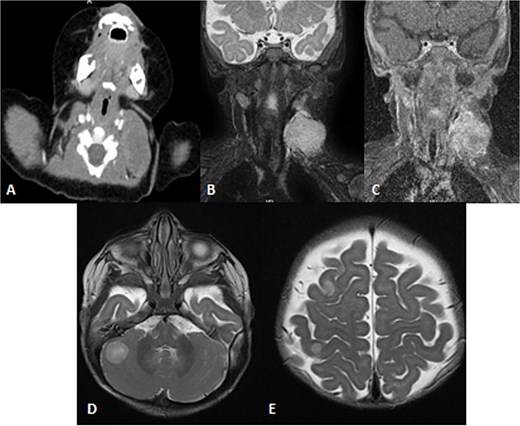

A 2-month-old girl was being followed for a suspected hemangioma on her left hand since birth. She was initially started on oral propranolol therapy but only received one dose, due to family concerns about possible side effects. The patient presented at the emergency room because of ulceration. It was observed clinically that the lesion had grown from 1.5 × 1.5 cm to 4 × 2 cm (Fig. 5). A biopsy of the lesion was taken. Ultrasound showed a partially defined large heterogeneously hyperechoic mass with internal vascularity on color Doppler with arterial and venous waveform giving atypical features of hemangioma (Fig. 6). Biopsy was done using FoundationOne Heme. The result showed stable microsatellite status and when we tested the tumor mutational burden, it showed two mutations per megabase. On MRI, a large lobulated subcutaneous soft tissue mass measuring 3.7 × 6.1 × 4.6 cm in dimensions was seen originating from the medial aspect of the left hand (Fig. 7). Internal flow voids, intermediate signal intensity on T1-weighted images, hyperintense signal on short tau inversion recovery (STIR)-weighted images, and noticeable heterogeneous enhancement on postcontrast sequences were all observed in the lesion. These imaging results raised suspicions of a malignant lesion.

MRI of left hand mass. (A) Axial T1WI shows a huge homogenous isointense mass to the corresponding hand muscles signal intensity, which is seen along the medial aspect of left hand. (B and C) Coronal STIR demonstrate heterogeneous diffuse high signal intensity of the lesion and appears inseparable with sign of invasion to the fourth and fifth digits extensor compartment/tendons as well as presence of areas of signal void (arrow). (D and E) Axial and sagittal post-contrast T1 fat-saturated images show diffuse progressive intense enhancement of the lesion.